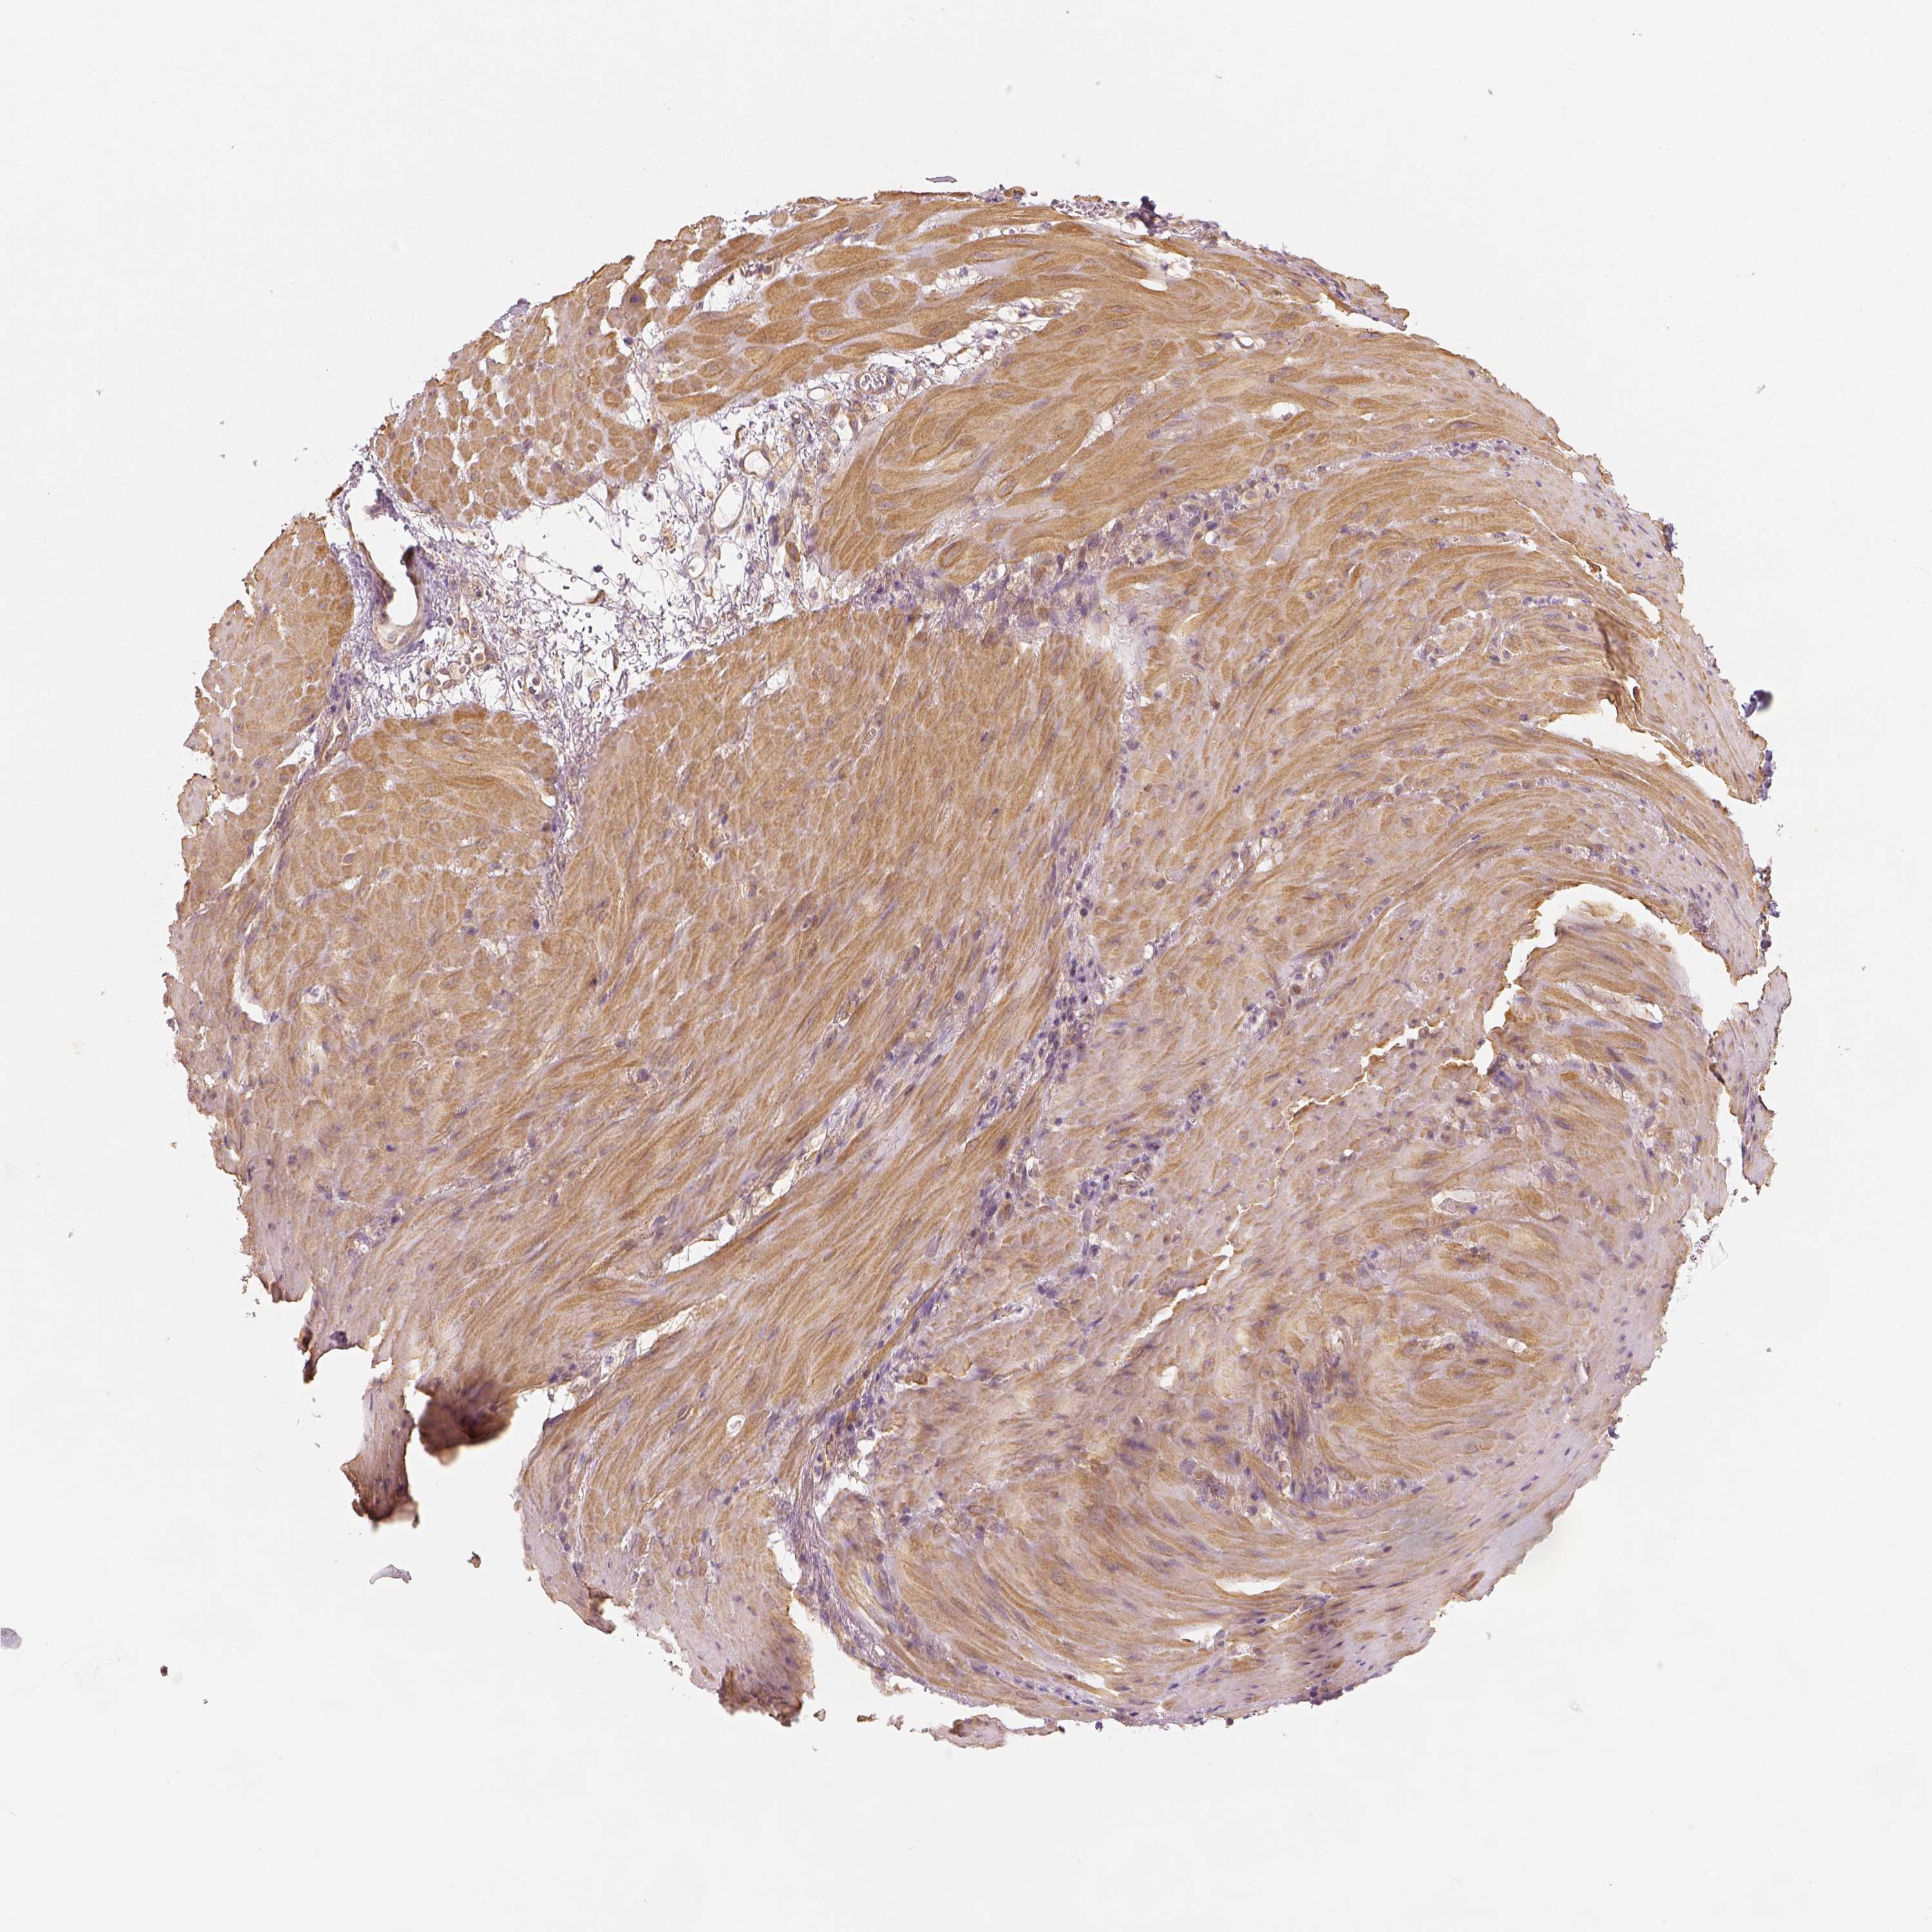

STOMACH CANCER - Protein expressioni

A mouse-over function shows sample information and annotation data. Click on an image to view it in a full screen mode. Samples can be filtered based on level of antibody staining by selecting one or several of the following categories: high, medium, low and not detected. The assay and annotation is described here.

Note that samples used for immunohistochemistry by the Human Protein Atlas do not correspond to samples in the TCGA dataset.

Antibody stainingi

Antibody staining in the annotated cell types in the current human tissue is reported as not detected, low, medium, or high, based on conventional immunohistochemistry profiling in selected tissues. This score is based on the combination of the staining intensity and fraction of stained cells.

Each image is clickable and will lead to virtual microscopy that enables deeper exploration of all samples and also displays staining intensity scores, fraction scores and subcellular localization as well as patient and tissue information for each sample.

Antibody HPA073653

Staining

High

Medium

Low

Not detected

Intensity

Strong

Moderate

Weak

Negative

Quantity

>75%

75%-25%

<25%

None

Location

Nuclear

Cytoplasmic/membranous

Cytoplasmic/membranous,nuclear

Adenocarcinoma, NOS